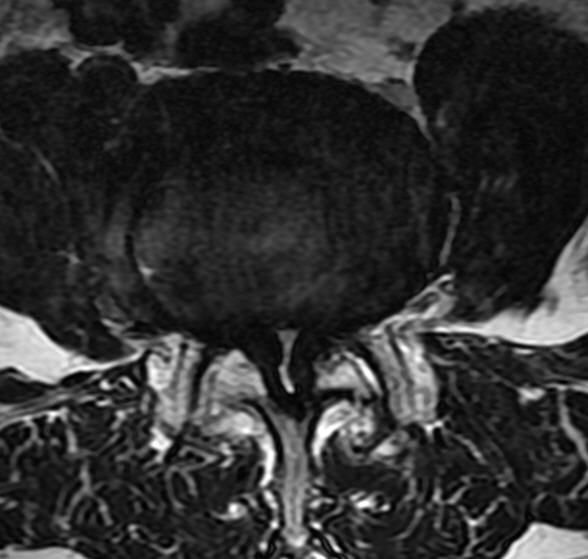

MRI

可提供腰椎管的矢状面、冠状面和轴位横断面上的影像。椎管狭窄以T2加权像显示较好,脑脊液为高信号,产生所谓“脊髓造影”的效果,而骨质增生,骨赘、间盘均为低信号,能清晰地显示椎管狭窄,以及对脊髓的压迫情况。但对肥大的黄韧带、骨质增生等的判断则不如较高清晰度CT扫描。

腰椎正常MRI解剖。

腰椎管狭窄MRI表现。